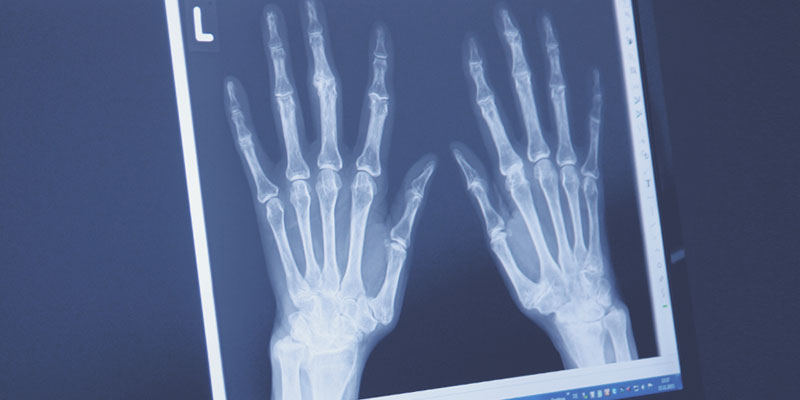

Röntgenuntersuchungen - unverzichtbar für die Diagnostik

Röntgenuntersuchungen sind auch heute in der Abklärung und Verlaufsbeurteilung rheumatischer und osteologischer Erkrankungen unverzichtbar.

In der Röntgenabteilung, die wir gemeinsam mit anderen Kollegen in unserem Ärztehaus betreiben, wird mit modernster digitaler Technik und geringer Strahlenbelastung gearbeitet.